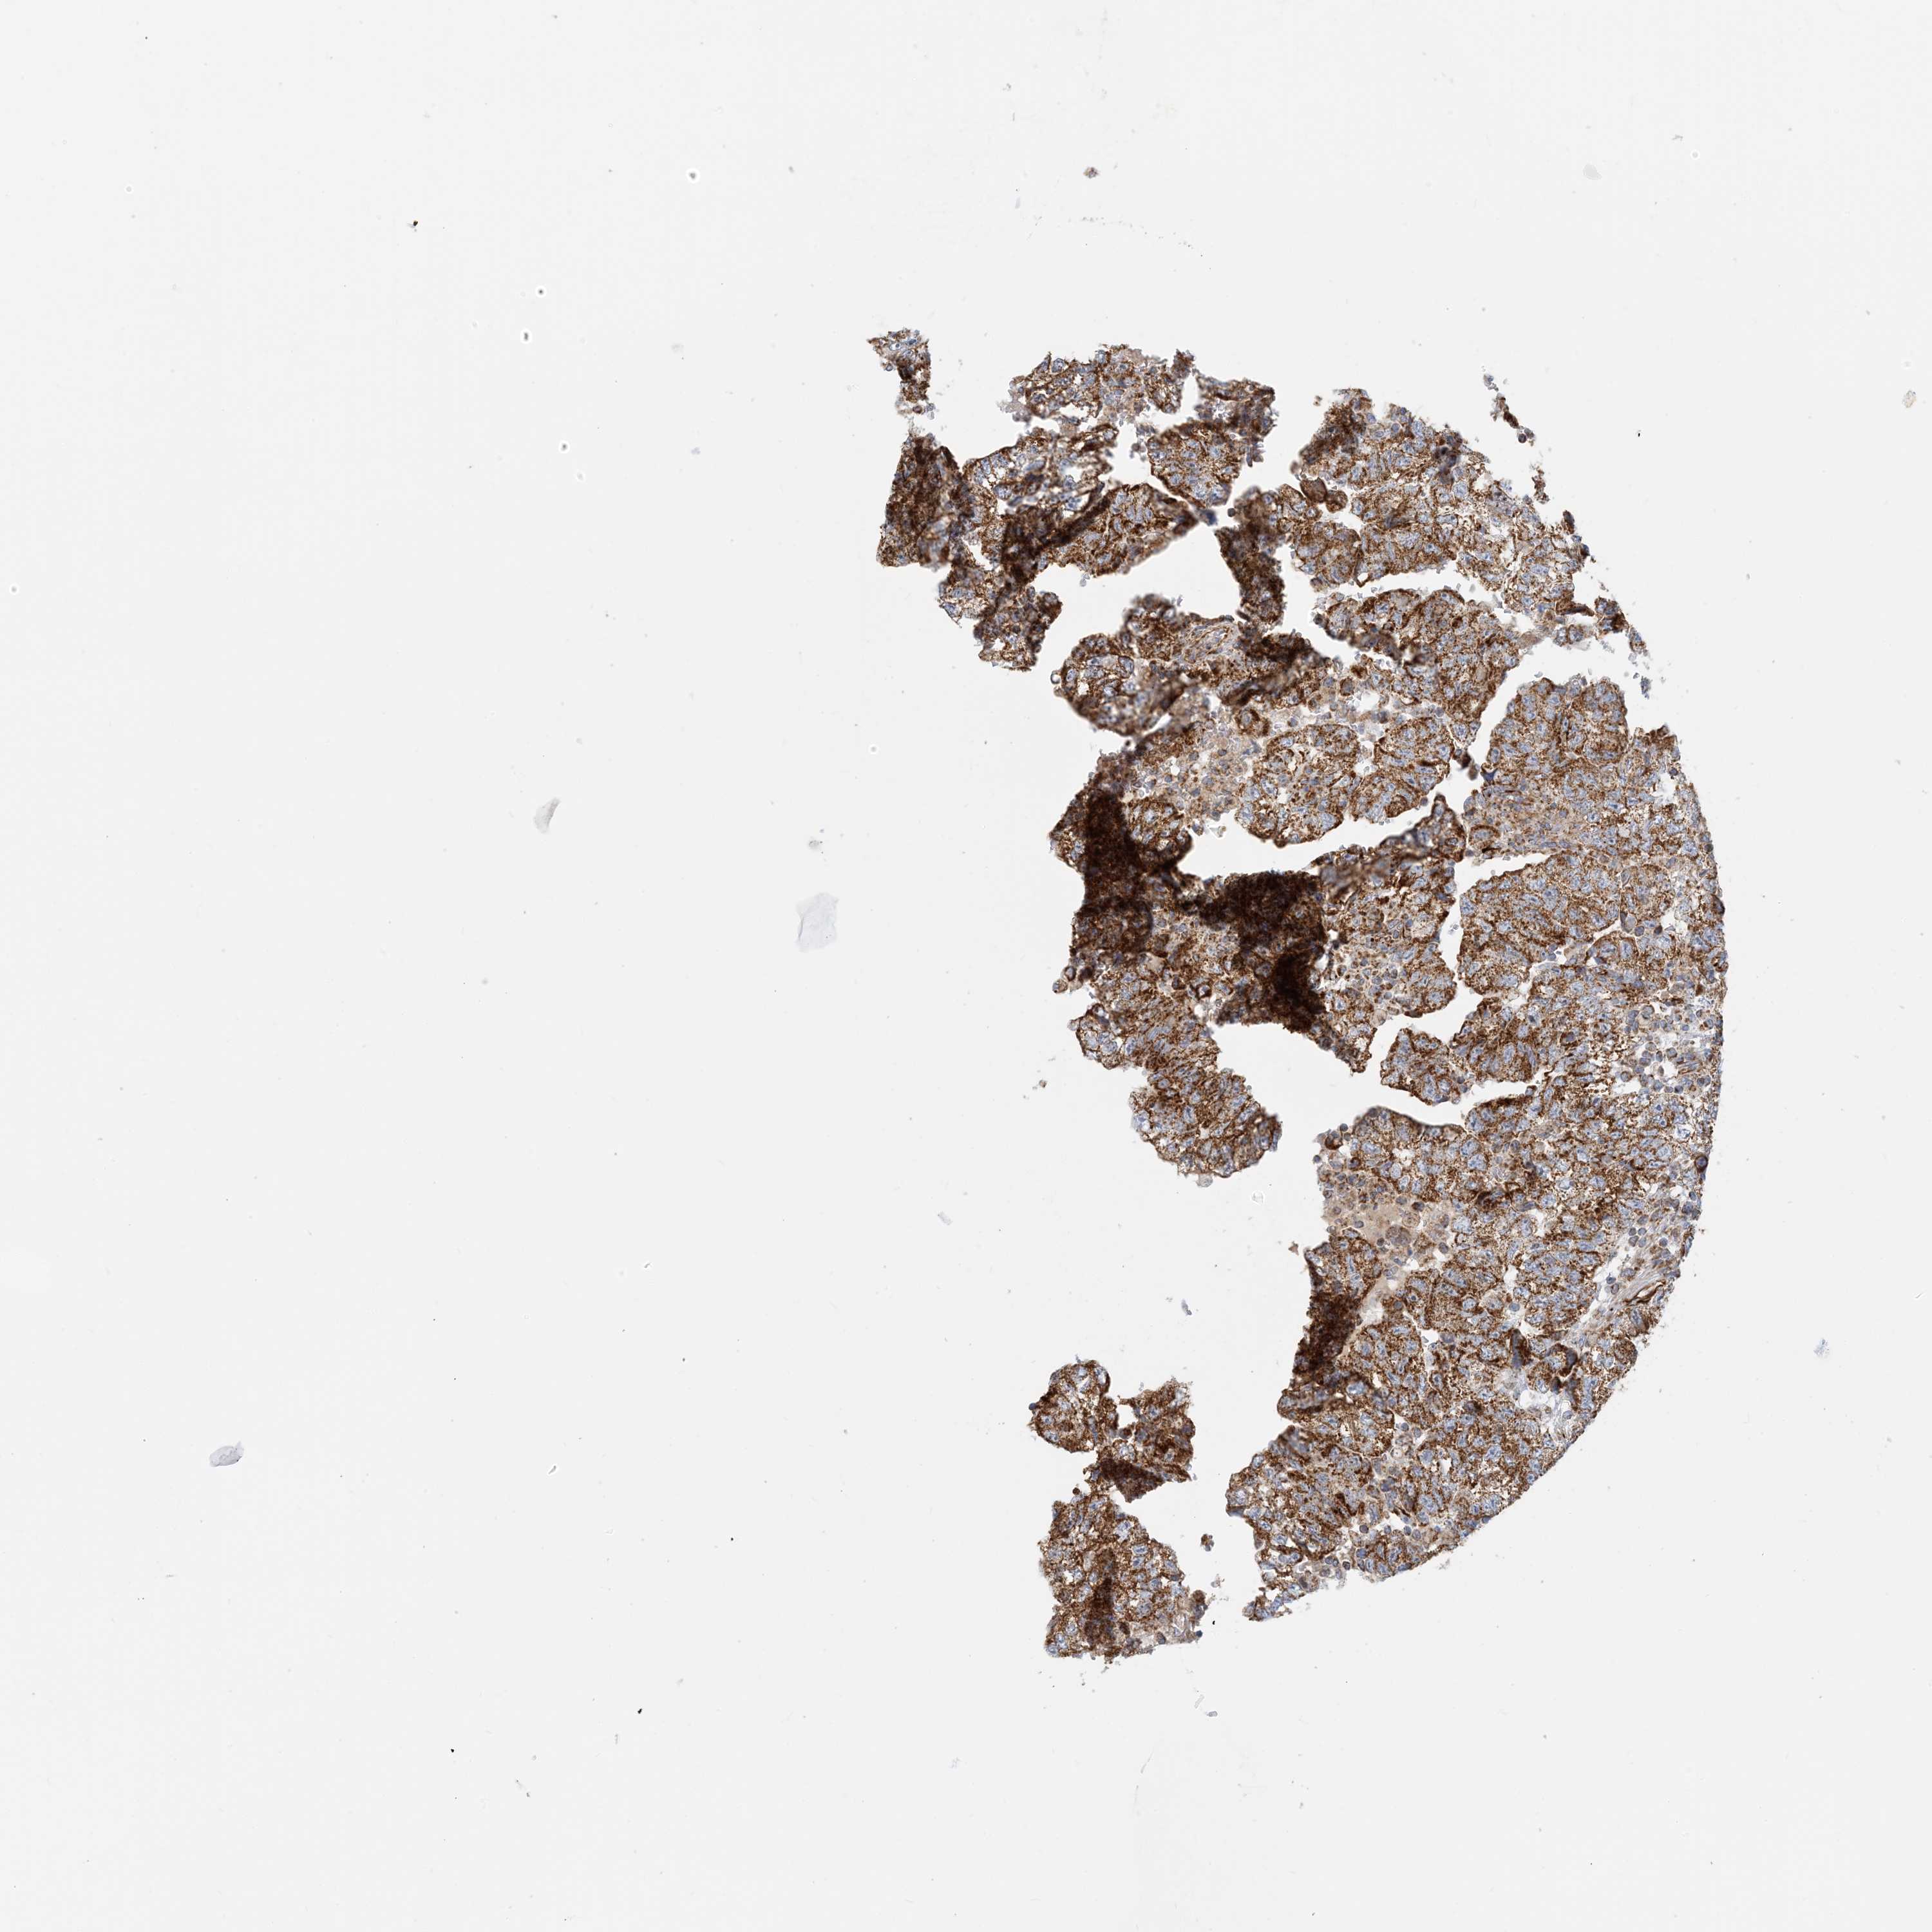

TESTIS CANCER - Protein expressioni

A mouse-over function shows sample information and annotation data. Click on an image to view it in a full screen mode. Samples can be filtered based on level of antibody staining by selecting one or several of the following categories: high, medium, low and not detected. The assay and annotation is described here.

Note that samples used for immunohistochemistry by the Human Protein Atlas do not correspond to samples in the TCGA dataset.

Antibody stainingi

Antibody staining in the annotated cell types in the current human tissue is reported as not detected, low, medium, or high, based on conventional immunohistochemistry profiling in selected tissues. This score is based on the combination of the staining intensity and fraction of stained cells.

Each image is clickable and will lead to virtual microscopy that enables deeper exploration of all samples and also displays staining intensity scores, fraction scores and subcellular localization as well as patient and tissue information for each sample.

Antibody HPA031966

Staining

High

Medium

Low

Not detected

Intensity

Strong

Moderate

Weak

Negative

Quantity

>75%

75%-25%

<25%

None

Location

Nuclear

Cytoplasmic/membranous

Cytoplasmic/membranous,nuclear

Carcinoma, Embryonal, NOS

Seminoma, NOS